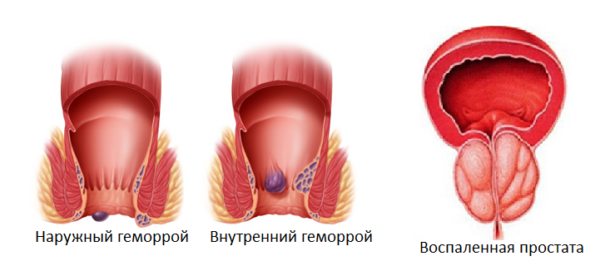

Гимнастика Кегеля для мужчин: упражнения для простаты